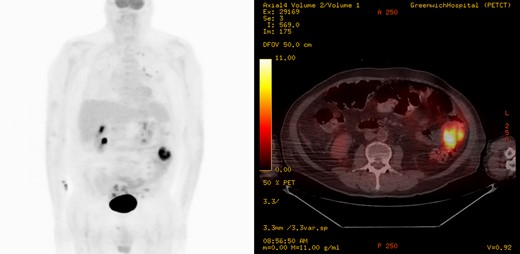

An urgent diagnostic laparoscopy was performed during which a hyperchromic, obstructing mass in the ileum was found (Fig. 3). No additional intraabdominal lesions were visualized. The portion of small bowel was extracorporealized, resected, and a primary stapled anastomosis was performed. The specimen revealed malignant melanoma (Fig. 4), positive for Melan A and S100 immunostains (Fig. 5) and for BRAF V600K mutation. A PET scan was finally performed 3 days postsurgery in which increased uptake was seen in the left lateral abdomen and in multiple bilateral pulmonary nodules (Fig. 6). He was discharged to a rehabilitation center.

Coronal and axial images of a positron emission tomography showing high metabolic activity in the small intestine within the left lateral abdomen.